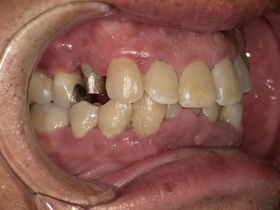

治療前の状態|詰め物の劣化と二次虫歯

診察の結果、以下の問題が確認されました。

■ 二次虫歯(再発虫歯)

詰め物と歯の隙間から細菌が侵入し、

👉 内部で虫歯が進行している状態

■ 適合不良(段差・隙間)

- 汚れが溜まりやすい

- 歯周病リスク増加

■ 噛み合わせの乱れ

欠けた状態を放置していたため、

👉 他の歯に負担がかかっていました

症例結果|Before / After

Before

- 詰め物が脱離

- 清潔感に欠ける状態